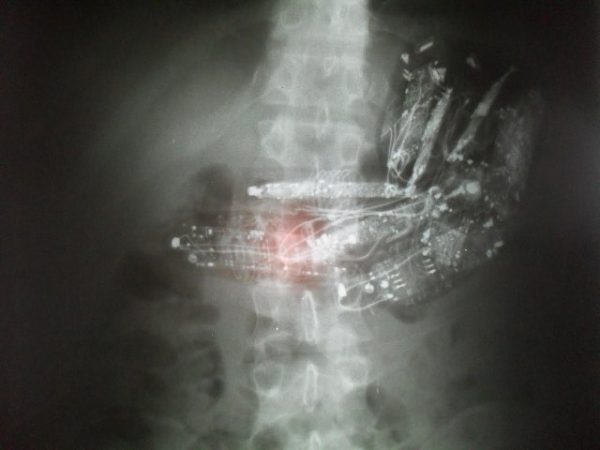

Após passar pelo exame de raios-X, foram descobertos dez minicelulares com fone de ouvido no estômago do terceiro preso envolvido. No mesmo dia, foi feita a cirurgia de retirada dos objetos e o preso se encontra internado para recuperação, segundo a SAP.